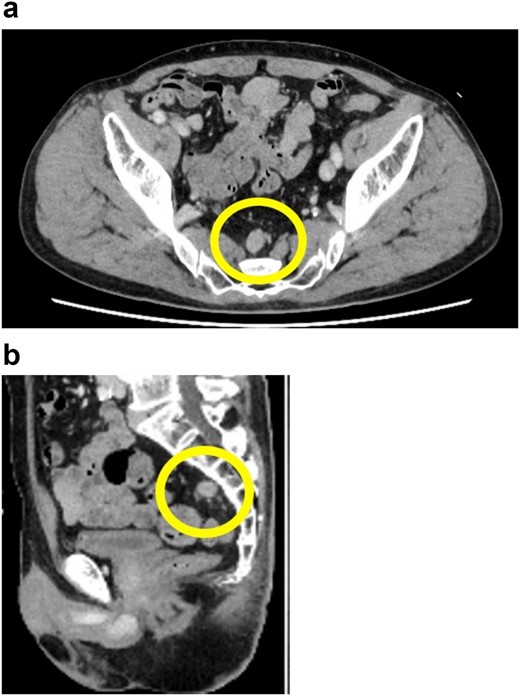

A 72-year-old man diagnosed with NSCLC was referred for possible surgical treatment of a solitary nodule detected in the mesorectum. His medical history included hypertension and endoscopic resection of colonic polyps, with no prior thromboembolism. He had received combined medical treatment for NSCLC (cT4N0M0, stage IIIA) (Fig. 1), including four courses of cisplatin and docetaxel chemotherapy with a 60 Gy/30 fractions radiation dose, followed by 1 year of consolidation therapy with durvalumab (640 mg/body). The patient tolerated the treatment well, achieving a complete response 13 months before presentation (Fig. 2). However, the mesorectal nodule was incidentally discovered during surveillance CT after NSCLC treatment completion. It was round, 15 mm in diameter, showed contrast enhancement, and was near the mesorectal vessels (Fig. 3a and b). An FDG PET/CT scan revealed a solitary mesorectal nodule with an SUVmax of 10.3 (Fig. 4). Consequently, the radiologist suggested differential diagnoses of malignant lymphoma and metastatic lymph nodes from the urinary or lower gastrointestinal tract, as NSCLC typically does not metastasize to mesorectal lymph nodes. No other abnormal FDG uptake was observed. Laboratory tests showed normal levels for tumor markers, including carcinoembryonic antigen, sialyl Lewis X (SLX), squamous cell carcinoma antigen, neuron-specific enolase, cytokeratin fragment (CYFRA), progastrin-releasing peptide, and blood coagulability was within the normal range. Total colonoscopy revealed no neoplastic lesions, and urinary cytology showed nonmalignant urothelial cells. Noninvasive diagnostic approaches, including endoscopic or CT-guided biopsy, were extensively discussed but deemed difficult because of anatomical restrictions, risk of dissemination, and procedure-related complications (such as bleeding or perforation). Because of the potential malignancy and need for en-bloc resection, we opted for surgical resection using a standardized laparoscopically assisted mesorectal excision technique. During rectal dissection, the nodule was not visible through the posterior and lateral sides because it was completely embedded in the mesorectum. Therefore, a Pfannenstiel incision was made in the lower abdomen to exteriorize the rectum after the division of the proximal colon. The nodule was confirmed by direct palpation, marked with a stitch, and subsequently removed after intracorporeal transection of the distal rectum. We inspected the resected specimen and confirmed that the nodule was incorporated (Fig. 5a and b). A colorectal anastomosis was then performed using a double-stapling technique with a circular stapler. The postoperative course was uneventful, except for a slight elevation of the d-dimer level (up to 3.26 μg/ml) on postoperative Day 7, which normalized spontaneously without intensive anticoagulation therapy. The patient was discharged on postoperative Day 10. Pathological examination revealed that the 7-mm white nodule was an intravenous organized thrombus in the mesorectum surrounded by granulation tissue, with no malignancy observed (Fig. 6a and b). Postoperatively, the patient did not require additional chemotherapy or anticoagulation therapy. During the 16-month follow-up, no radiological evidence of NSCLC recurrence and thromboembolism was detected (Fig. 7).

Preoperative 18F-fluorodeoxyglucose (FDG) positron emission tomography (PET)/computed tomography (CT) image. The circle highlights the nodule located in the mesorectum with a maximum standardized uptake value (SUVmax) of 10.3.

FDG PET/CT is widely used for clinical staging of malignancy and detecting postoperative recurrence due to its ability to provide relevant metabolic information. It is well-known that SUVmax is higher for malignant lesions compared to benign ones, reflecting their active glucose metabolism. A previous study showed that FDG PET/CT has good diagnostic performance for staging distant metastasis in patients with NSCLC [7]. Additionally, SUVmax is useful for diagnosing venous thromboembolism (VTE) [8]. Several studies have demonstrated the efficacy of FDG PET/CT in distinguishing venous tumor thrombus from venous bland thrombus. Hu et al. [9] reported that tumor embolisms associated with portal vein thrombosis had a significantly higher SUVmax than simple thrombi, with tumor embolisms showing an SUVmax of 6.37 ± 2.67 and simple thrombi showing an SUVmax of 2.87 ± 1.47. Similar results were found in studies on renal cell carcinoma and hepatocellular carcinoma [10–12]. In our present case, the SUVmax of the mesorectal nodule was 10.3, which reasonably led to suspicion of malignancy.

The underlying mechanism of the solitary mesorectal thromboembolism in this case remains unclear. Patients with malignant diseases are at high risk for VTE, and cancer-associated thrombosis is a major complication among patients with lung cancer [13]. The risk of cancer-associated thrombosis is influenced by patient and cancer characteristics. For instance, conditions such as anemia, chronic obstructive pulmonary disease, and obesity can increase the risk of VTE [14]. Additionally, chemotherapy is an independent risk factor for VTE in patients with lung cancer [13]. A large retrospective study published in 2011 reported that 18.1% of patients treated with cisplatin-based chemotherapy experienced thromboembolic events during treatment or within 4 weeks of the last treatment dose [15]. While our patient did not have comorbidities associated with risk factors for VTE, we posit that cisplatin-based chemotherapy might have contributed to the development of thromboembolism. To the best of our knowledge, no previous studies have reported solitary thromboembolism in the mesorectum. Notably, given the high SUVmax of the nodule during FDG PET/CT, it was challenging to rule out malignancy in our case.